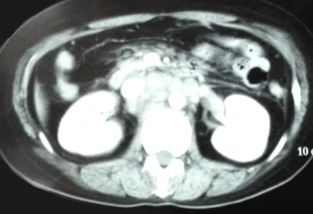

腹部CT:肝胃韧带、肝十二指肠韧带、门腔间隙、胰腺周围、腹主动脉周围多发大小不等的软组织结节影,部分融合成团。

腹膜后淋巴结治疗3月(4周期)